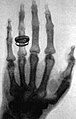

-

Historische Aufnahme einer Hand mit Ring (Röntgen, 23. Januar 1896) -